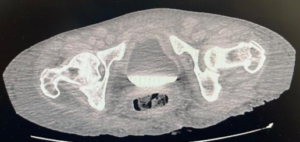

Paciente feminina, 68 anos, negra, que vive com HIV há cerca de 18 anos em tratamento irregular estava internada em unidade hospitalar para investigação de neoplasia linfoproliferativa e durante investigação foi solicitada tomografia computadorizada de abdome e pelve (relato de grande ureterohidronefrose direita e provável compressão ureteral extrínseca ao nível dos vasos ilíacos, com eliminação de contraste do ureter esquerdo em fase tardia), sendo pedido parecer a urologia.